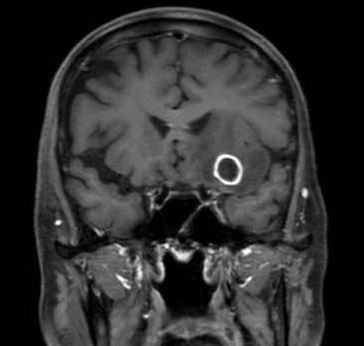

核医学検査は放射性同位元素を用いた画像検査です。がん診療においては転移箇所の検索に行われます。骨シンチグラフィ検査は、骨の代謝を画像化することができ、骨への転移を比較的早期に見つけることができます。

骨シンチグラフィ(乳癌全身骨転移)